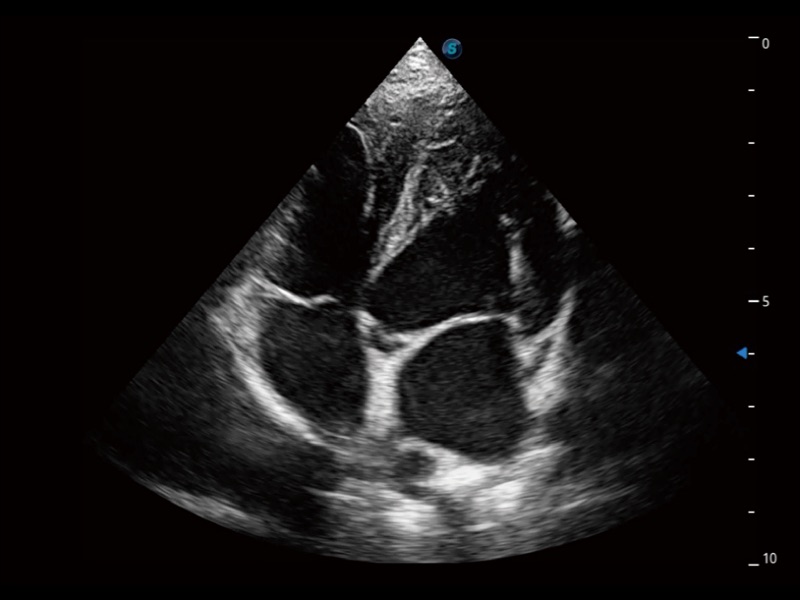

通过360度任意调节3条M型取样线,在同一心动周期上观察心脏不同位置的运动曲线,得到准确的心功能测量数据,有效评估心肌运动及左心室功能。

实时用颜色表示心肌组织运动,观察和定量组织的运动情况,对快速检测与评估心肌的灌注和活性、电传导及心肌收缩和舒张功能等均能提供重要的诊断信息。

为精细结构及组织边缘提供高清晰度的图像和更大的成像视野。帮助减轻医生的用眼疲劳,快速精准获得测量的数据。